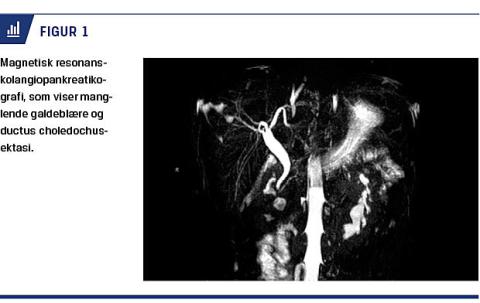

Få uger efter blev han indlagt akut pga. forværring af smerterne. Fornyede biokemiske undersøgelser viste fortsat upåfaldende resultater, og der blev målt følgende værdier: leukocytter: 6,9 mia./l; C-reaktivt protein < 3 mg/l; bilirubin: 10 μmol/l; alaninaminotransferase: 71 E/l og basisk fosfatase: 102 E/l. Der var normale vitale parametre. Pga. den tidligere beskrevne ductus choledochus-ektasi blev der foretaget en ny UL-skanning. Denne rejste mistanke om manglende galdeblære, hvilket blev bekræftet ved en efterfølgende magnetisk resonans-kolangiopankreatikografi (MRCP) (Figur 1). Herudover fandt man hesteskonyre samt vena cava inferior lokaliseret til venstre for aorta abdominalis. For at udelukke iskæmi som følge af afklemte kar pga. abnorm beliggenhed, blev udredningen suppleret med CT-angiografi, som blandt andet viste normalt kalibrerede mesenterielkar. Under indlæggelsen blev der også foretaget gastroskopi, som viste makroskopisk normale forhold. Patientens smerter remitterede under indlæggelsen, og han blev udskrevet til